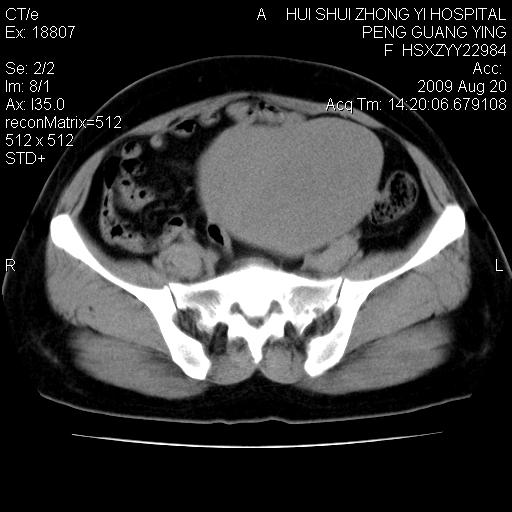

标题: CT21707:女,42岁,因发现下腹部包块2月。 [打印本页]

标题: CT21707:女,42岁,因发现下腹部包块2月。

增强看看,倾向于子宫肌瘤并囊变或腺肌征,宫腔少量积液。

病灶来源——子宫?附件?

从平扫角度看本人还是倾向于子宫肌瘤诊断,宫腔少量积液。

目前的影像表现显示肿块位于腹腔及盆腔,但具体定位,分清来源较困难,是否来源于卵巢、子宫无法定论,子宫直肠及子宫膀胱周围脂肪间隙尚较清晰,如果患者有过腹腔好或者盆腔手术史,也可以形成不典型的血中,最好手术后定为定性,我期待结果。

软组织密度,与子宫一致。双侧卵巢形态、密度好,不支持来源于卵巢。